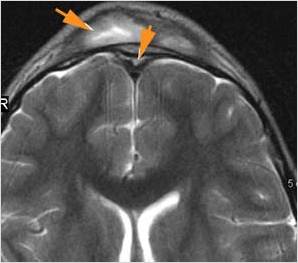

There is evidence of thrombus, thrombophlebitis or other occlusive or inflammatory process of the cortical veins, sphenoparietal sinus or sagittal sinus. [Yes/No]

There is evidence of thrombus, thrombophlebitis or other occlusive or inflammatory process of the cavernous sinus. [Yes/No]